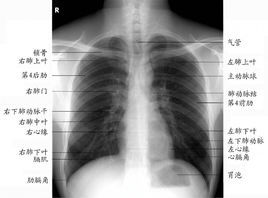

肺部鈣化點是肺結核痊癒的形式之一。正常肺組織是由肺泡、淋巴微血管、細支氣管等組成,呈粉紅色。若有相當數量和毒力強的結核桿菌侵入肺組織並在裡面生長繁殖,產生代謝產物,使肺組織受到破壞,出現好像變質的乳酪一樣的物質,使正常的結構、生理功能消失。醫學上稱為乾酪樣壞死。壞死物偏於酸性,不易液化吸收,能長期存在。在機體抵抗力強,或者化療後,乾酪樣病灶中的結核桿菌代謝低落,繁殖能力被削弱,病灶失水而乾燥,碳酸鈣和磷酸鈣沒著形成鈣化。

肺部的鈣化斑只是人體肺細胞壞死之後產生的一些特殊的變異,人體每天都在進行新陳代謝,一些細胞壞死是正常現象,壞死之後,因為自身循環不暢,從而在肺部中沉著下來,形成鈣化斑,在胸透下顯示出很像是結石的亮點。一般情況下,這種斑點在胸透檢查中只有0.5cm左右。鈣化斑如同皮膚上長的痣,只是一些壞死細胞的沉著,大多數是良性的,而且病人本身大多數都沒有什麼症狀,一般情況下不用處理。